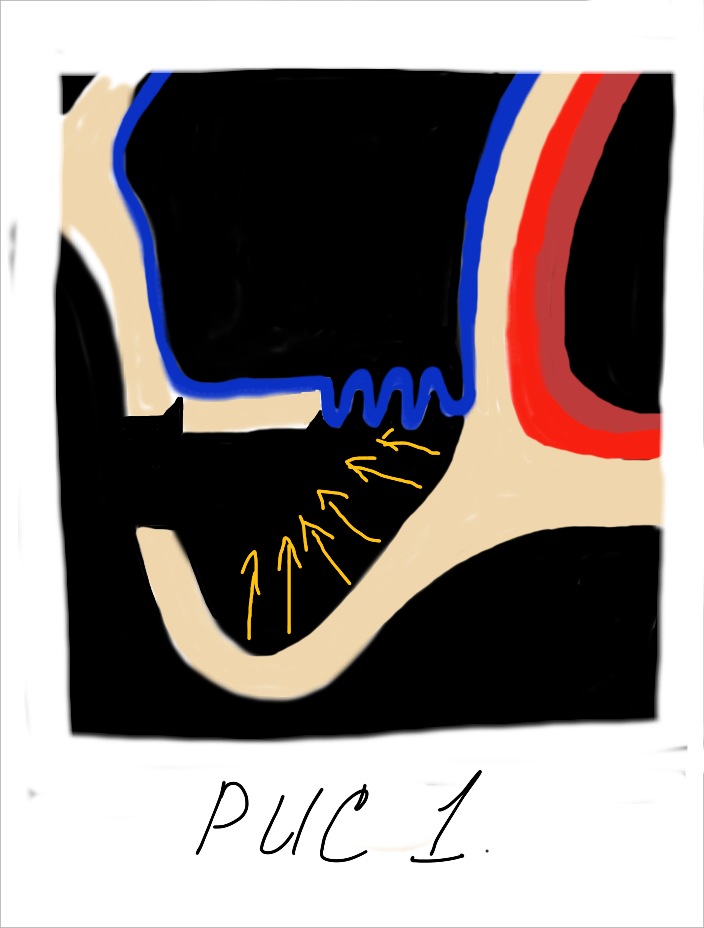

- Отслаивание слизистой пазухи.

При этом, чем выше мы поднимаем слизистую пазухи тем больше кровоснабжения из соседних участков мы можем получить (рис 2).

При этом, чем выше мы поднимаем слизистую пазухи тем больше кровоснабжения из соседних участков мы можем получить (рис 2).  Сосудистая сеть наружной стенки носа многослойная и обильная. Следовательно, получить кровоснабжение из данного источника очень легко. Для этого необходимо как можно выше отсепарировать слизистую пазухи с носовой стенки. Благодаря этому мы получаем несколько плюсов. Во первых, напряжение слизистой уменьшается она становиться складчатой. Это предупреждает возникновение разрывов и трещин во время аугментации. Во вторых, мы получаем доступ к месту с обильным кровоснабжением которое крайне необходимо для последующего костеобразования и ремоделирования костной ткани.

Сосудистая сеть наружной стенки носа многослойная и обильная. Следовательно, получить кровоснабжение из данного источника очень легко. Для этого необходимо как можно выше отсепарировать слизистую пазухи с носовой стенки. Благодаря этому мы получаем несколько плюсов. Во первых, напряжение слизистой уменьшается она становиться складчатой. Это предупреждает возникновение разрывов и трещин во время аугментации. Во вторых, мы получаем доступ к месту с обильным кровоснабжением которое крайне необходимо для последующего костеобразования и ремоделирования костной ткани.